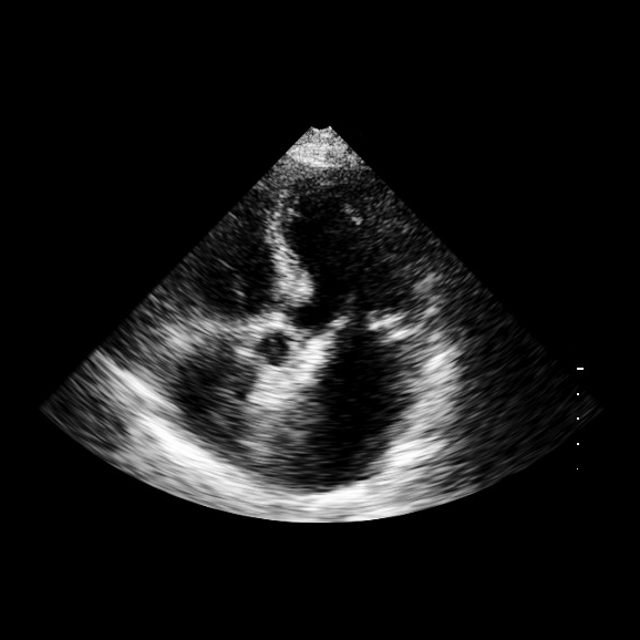

Landmark detection

We further evaluate EchoVLM on landmark detection using the public EchoNet-LVH dataset (duffy2022high), which benchmarks left ventricular hypertrophy (LVH) assessment from PLAX echocardiographic frames. The task requires predicting landmark coordinates for the interventricular septum (IVS), left ventricular internal dimension (LVID), and left ventricular posterior wall (LVPW), from which wall thicknesses are derived. For network architecture, we attach a UNETR style decoder to EchoVLM hatamizadeh2022unetr. Evaluation metrics include the mean absolute error (MAE) of the derived measurements (mm) and the average landmark error (Average L.E), defined as the Euclidean (L2) distance between predicted and ground-truth landmark coordinates (mm). The dataset is split into 20,254/2,275/683 frames for training, validation, and testing, respectively. We compare with a task-specific model DeepLabV3 (chen2017rethinking) and foundation model EchoApex. As shown in Table 4, EchoVLM achieves competitive performance, outperforming both baselines on IVS and LVID in both metrics.

We attach a UNETR-style decoder (hatamizadeh2022unetr) to EchoVLM for landmark prediction and train using a combination of GeneralizedDice and Focal losses (see Table 14). At inference, landmark coordinates are obtained from the predicted heatmaps as the centroids of thresholded activation regions. Performance is assessed using mean absolute error (MAE, in mm) of derived measurements and the average landmark error (Average L.E., Euclidean distance in mm) between predicted and ground-truth locations.

As summarized in Table 4, EchoVLM achieves competitive performance, outperforming both the task-specific baseline DeepLabV3 and the vision foundation model EchoApex on IVS and LVID measurements. These results confirm that our multimodal pretraining retains fine-grained spatial sensitivity required for clinical measurement tasks, providing reliable landmark localization in echocardiographic frames.